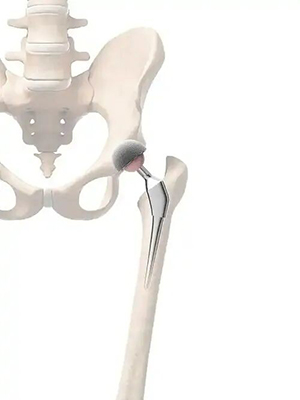

如今,人工全髋关节置换术的成熟应用,早已成为终末期髋关节疾病的“金标准”。该技术能彻底解除患者因关节软骨磨损、骨质增生或股骨头坏死引发的持续性疼痛与活动剧痛,使其无需依赖止痛药,轻松恢复安稳睡眠、久坐等日常功能,更能重建髋关节生理功能,让行动受限成为过去。对于范先生这类股骨头坏死合并关节外骨折的复杂病例,其手术步骤繁琐、操作难度大,北院骨三科团队针对性选用后外侧入路方式,兼顾髋关节置换与骨折内固定的切口需求,实现术野充分暴露、精准直达病灶。更重要的是,牢固的内固定让患者术后可尽早开展功能锻炼,大幅压缩住院与康复周期,为早期安全康复筑牢基础,真正实现“最小创伤、最大疗效”的微创目标,如同“精准拆弹”般完成高质量关节重建。

髋关节置换手术入路很多,比较常用的有后外侧入路、直接外侧入路、直接前方入路等。后外侧入路因为视野好,显露清楚,在临床上应用最为广泛;直接外侧入路,因为需要切开髋关节外侧最重要的一块肌肉——臀中肌,对其造成的损伤可能导致术后跛行,目前该入路在临床上使用逐渐减少。

后外侧入路方式开展髋关节置换术的适应人群主要包括以下几类:髋关节骨关节炎患者,股骨头坏死患者,股骨颈骨折、髋臼骨折等髋部骨折患者,复杂髋关节翻修患者,类风湿性关节炎等自身免疫性疾病患者,先天性髋关节发育不良患者,髋关节结核或肿瘤患者。